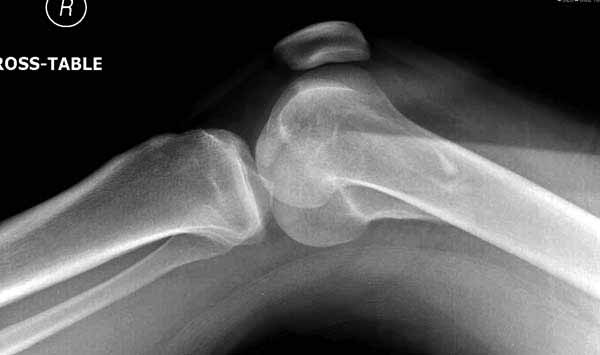

По снимку вроде одиночный простой мыщелковый перелом, и такой внутрисуставной перелом не обязательно дистрагировать на скелетном вытяжении, потому что не не нарушается непрерывность колонны с одной стороны. И для таких простых переломов подойдет любой метод: 95 градусная пластина, Lat. Condylar Butress пластина или ретроградный гвоздь. А для особых энтузиастов которые желают антеградную фиксацию, возможно легко найти трохантер у алкоголиков или дистрофиков. А вот у откормленных Макдональдскими гамбургерами? Если поискать у них тоже можно найти, но стоит ли?

У больных как в этом случае, с вовлечением двух мыщелков правильно, что сделали вытяжение до операции. Здесь имеется флексионный компонент на другой стороне, и я бы рекомендовал операцию делать из двух доступов. Сперва фиксировать медиальную колонну custom made пластиной, обычно 1/3 тубулярной пластиной в 4.5 мм, потому что пока производители опаздывают с медиальной пластиной.

Пластину надо устанавливать на апексе перелома, иначе фрагмент начнет сползать. А на второй стороне, если имеется большой одиночный фрагмент тогда проблем не бывает, и их можно собрать компрессирующими винтами. Проблема наступает тогда когда многофрагментраность на латеральной стороне, где надо применить комбинированный метод, иногда несколькими пластинами. Или сменой позиции установки пластины, чтобы максимально прикрыть перелом и создать боковую поддержку.